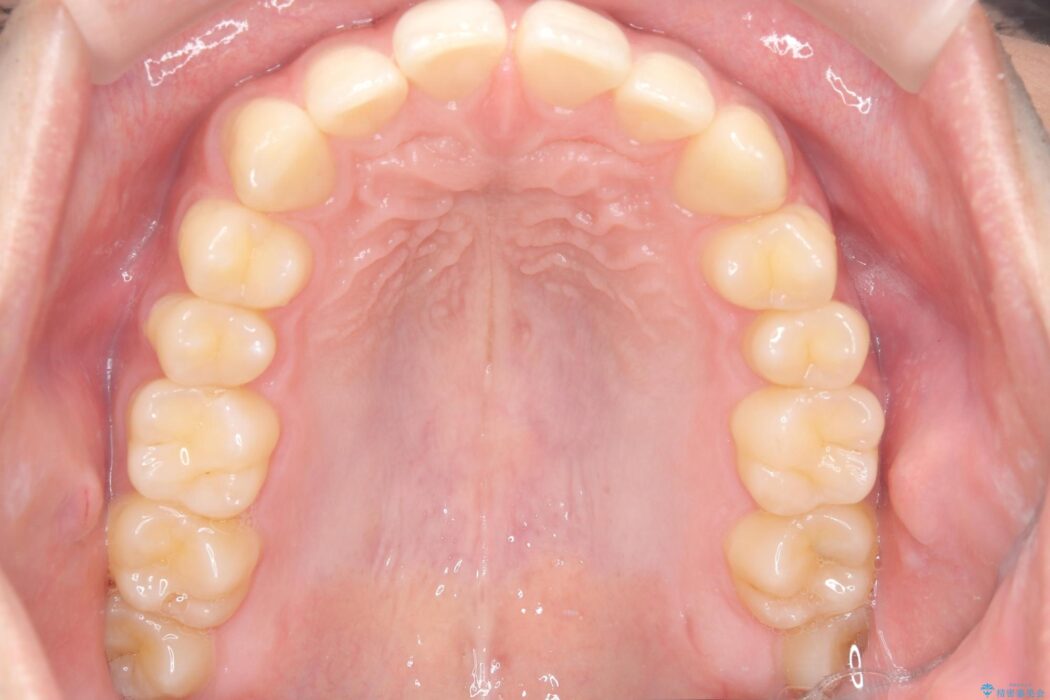

上の前歯のすきっ歯を治したいとご来院された患者様です。

上顎中切歯間の隙間の他にもフロスが抵抗なく入るスペースが上顎は数か所ありました。スペースを閉じ下顎の歯列弓との調和をとるためIPRを行いました。